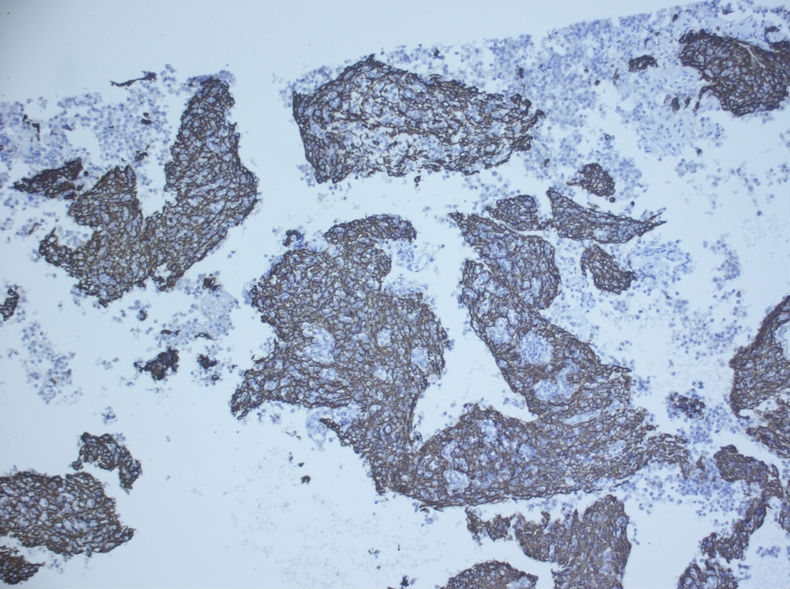

术后病理示:胸腺瘤(B3型为主)

根据腊块及免疫组化结果,我诊断了

(左胸壁)转移性胸腺瘤(B2型)

建议检查纵隔。

随访,纵隔发现一3.5×3cm肿块,术后病理示:胸腺瘤(B3型为型)

我当时就让病人等两天,等我把细胞腊块的结果出来后告诉他。

细胞腊块图片如下:

免疫组化结果:

随访,纵隔发现一3.5×3cm肿块,术后病理示:胸腺瘤(B3型为主)

肋间肿块切除的标本有的,形态和细胞腊块一致,属于胸腺瘤B2+B3型。